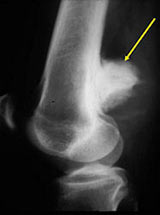

Radiographic imaging is used to help form a diagnosis. These include X-Ray, MRI, CT.

An example of an MRI is shown.